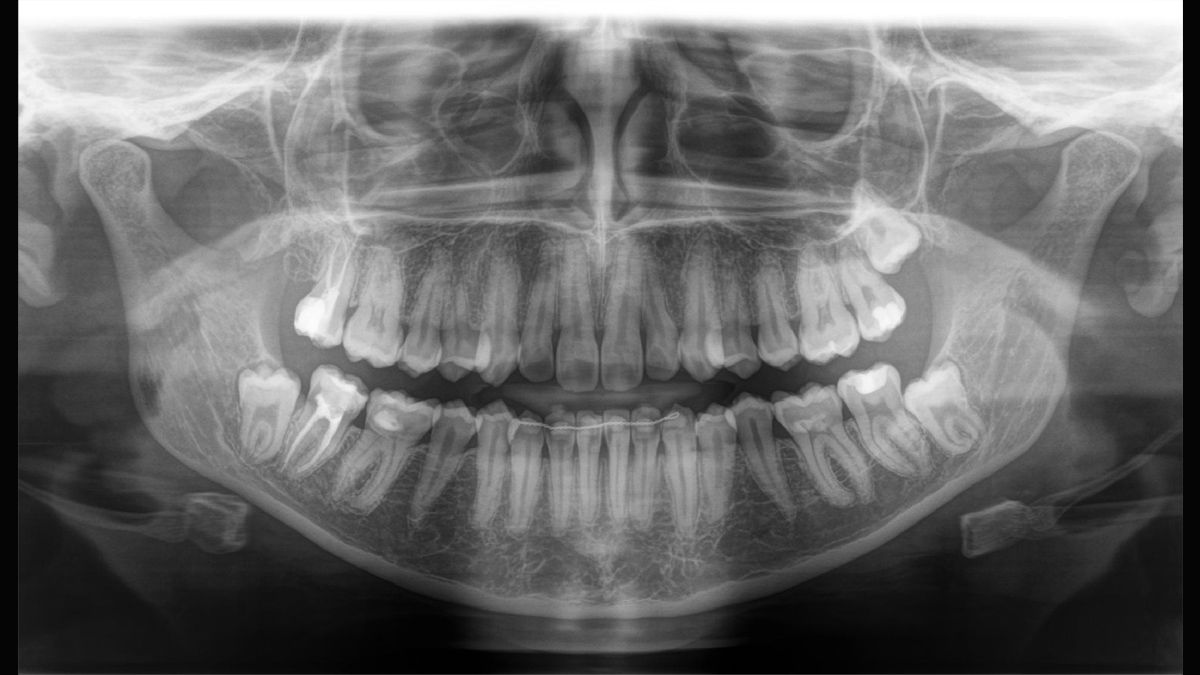

Tecnología Sharp Layer (SL)

La tecnología SL le permite generar multiples imágenes durante una única rotación. Los fragmentos con mejor enfoque se combinan automáticamente para formar una imagen de rayos X con nitidez incomparable (ideal para observar piezas multiradiculares).

Direct Conversion Sensor

La tecnología DCS convierte los rayos X directamente en señales eléctricas sin pérdida de información debida a la conversión de la luz. Permite obtener imágenes de radiografía panorámicas de elevado contraste con una calidad excepcional.

Algoritmo de software ASTRA

ASTRA mejora considerablemente la calidad de las imágenes panorámicas 2D y cefalométricas. Este algoritmo de reconstrucción estructurado anatómicamente genera una imagen con mayores contrastes sin la aparición de bordes indefinidos.